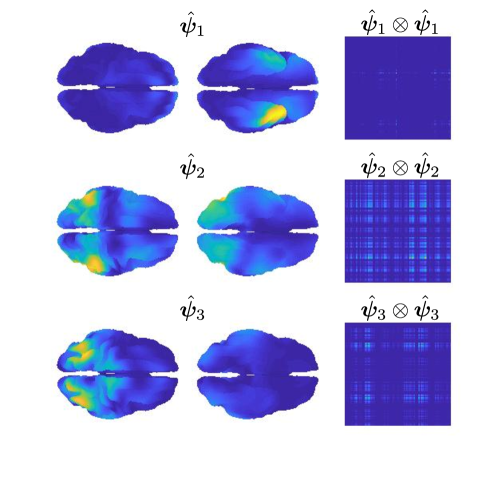

The second part of the analysis focuses on applying the proposed methodology to a multi-subject setting. Specifically, different subjects are considered. For each subject, the 6 minutes scan is used to compute a covariance matrix, resulting in covariance matrices . The template geometry in Figure 10 is used as a model of the brain space. Algorithm 2 is then applied to find the PC covariance functions on the template brain, associated with . We run the algorithm for iterations, and choose the regularizing parameter to be by inspecting the L-curve plot in the right panel of Figure B.2. The results for are shown in the appendices. The energy maps of the estimated functions , and and the associated first three covariance functions , and , are shown in Figure 13. High intensity areas, in yellow, indicate which areas present high average connectivity. In Figure 14, we show the subject-specific associated variances, both in the sensors space and the brain space.

The presented methodology opens up the possibility to understand population level variation in functional connectivity, and indeed, whether, just as we need different forward operators for individuals (due to anatomical differences), we should also be considering both population and subject-specific connectivity maps when analyzing connectivity networks. In fact, it is of interest to note that in both the single and multi-subject settings, the areas with high interconnectivity, displayed in yellow in Figure 11 and 13, seem to be at least partially overlapping with the brain’s default network (Buckner et al., 2008; Yeo et al., 2011). The brain’s default network consists of the brain regions known to have highly correlated hemodynamic activity (i.e. highest functional connectivity levels), and to be most active, when the subject is not performing any specific task. An image of the spatial configuration of the default network can be found, for instance, in Figure 2 of Buckner et al. (2008). From the plots of the associated variances in the sensors space (left panel of Figure 12 and Figure 14) we can see that these areas are also the ones that show high variability in connectivity across time or across subjects. This might suggest that the brain’s default network is also the brain region that shows among the highest levels of spontaneous variability in connectivity.

The plots of the variances on the brain space (right panel of Figure 14), when compared to those on the sensors space (left panel of Figure 14), demonstrate that these type of studies are highly sensitive to the choice of the regularization, not only in terms of spatial configuration of the results, but also in terms of estimated variances on the brain space. With a naive ‘first reconstruct and then analyze’ approach, where the reconstructed data on the brain space replace those observed on the sensors space, this issue could go unnoticed, as the variability that does not fit the chosen model is implicitly discarded in the reconstruction step and does not appear in the subsequent analysis. Also, importantly, our analysis deals with statistical samples that are entire covariances, overcoming the limitations of seed-based approaches, where prior spatial information is required to choose the seed. Seed locations are usually informed by fMRI studies and this comes with the risk of biasing the analysis when comparing electrophysiological networks (MEG) and hemodynamic networks (fMRI).

In Figure B.7-B.8 we show the estimated PC covariance functions and associated variances from the multi-subject functional connectivity study on subjects with regularization parameter .

Acknowledgments. The authors would like to thank the anonymous reviewers and the member of the Editorial Board for their useful and constructive comments.